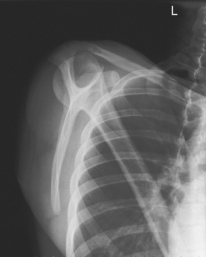

Transthoracic Lateral (Lawrence Method)

• Erect or supine (erect preferred with pain in scapula area)

• Gently abduct arm 90° if possible, supinate hand (abduction results in less superimposition of scapula by ribs).